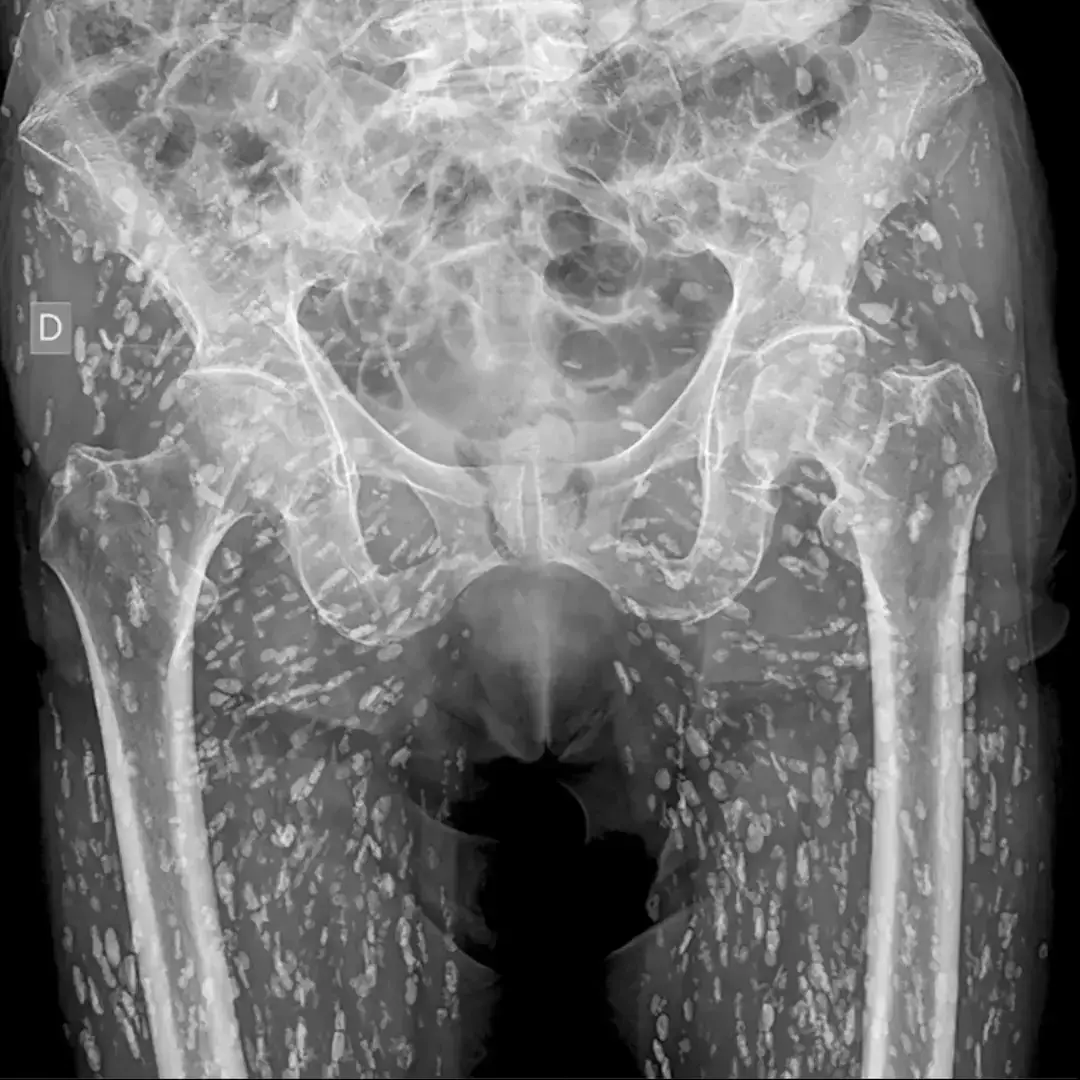

The gut-wrenching x-ray is of the lower-half of one patient's body, including their stomach, buttocks, and upper-thighs, all of which appear to be littered with thousands of small, unusually-shaped beings.

Writing online, Dr Ghali described the condition as 'cysticercosis', otherwise known as infestation caused by the 'pork tapeworm'.

These cysts have the ability to travel anywhere in the body, and in case of the patient in the x-ray, it appears as though they've infiltrated muscles around the hips and legs.

"What happens is they lodge here, and over time, they calcify," Dr Ghali went on. "And that gives them this classic appearance known as rice grain calcification."

Despite appearances, he added that such an infestation poses no real physical danger in this realm of the body, revealing that the patient only attended the emergency room after suffering a broken bone.